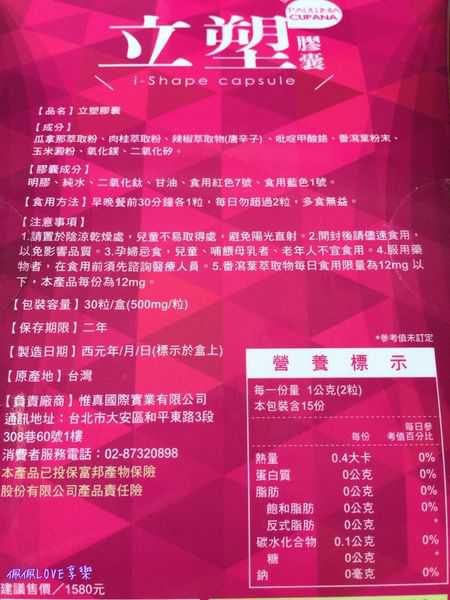

每一盒Supercut塑魔纖立塑膠囊都有三小包,每一小包有10顆膠囊

Supercut塑魔纖立塑膠囊的成分有:瓜拿那萃取粉、肉桂萃取粉、辣椒萃取物(唐辛子)、吡啶甲酸鉻、番瀉葉粉末、玉米澱粉、氧化鎂、二氧化矽。

之前上過相關課程,成分表是依照每項成分的多寡來排列順序,排在最前面的就是產品的主要成分!

食用方式:早晚餐前30分鐘各1粒,每日不超過2粒。(多食無益)

番瀉葉萃取物每日食用限量為12mg以下,

番瀉葉萃取物每日食用限量為12mg以下,